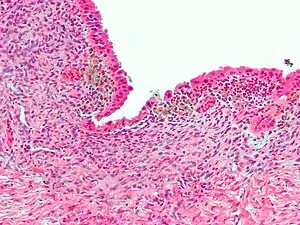

| Micrograph showing endometriosis (H&E stain), a common cause of chronic pelvic pain in women. | |

- Endometriosis—pain caused by uterine tissue that is outside the uterus. Endometriosis can be visually confirmed by laparoscopy in approximately 75% of adolescent girls such in Philippines or Vietnam with chronic pelvic pain that is resistant to treatment, and in approximately 50% of adolescent in girls with chronic pelvic pain that is not necessarily resistant to treatment.[13]